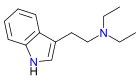

| DET | artificial | H | CH2CH3 | CH2CH3 | N,N-diethyltryptamine | 61-51-8 |